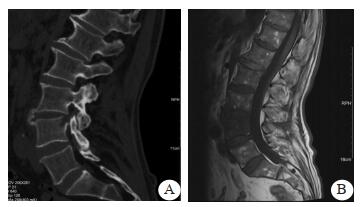

1 资料与方法男性患者, 63岁, 因“腰痛2个月, 突发腹痛3 h”于2018年12月28日收入本院急诊抢救室。患者腰背痛病史2个月, 曾在本院骨科门诊就诊。查体腰背有轻度叩痛, 弯腰活动有受限。神经系统查体阴性。本院CT检查示, 腰4椎体上缘局部骨质吸收、破坏, 椎旁软组织稍肿胀, 考虑感染性炎症可能(图 1A)。复查腰椎MRI示, 腰4椎体上缘局部骨质破坏, 腰3/4椎体斑片状骨髓水肿, 椎旁软组织水肿。提示腰3/4感染性脊柱炎(图 1B)。患者血沉及CRP升高, 诊断为腰椎感染。患者曾在当地医院进行治疗, 包括卧床休息、抗感染治疗。

| 图 1 患者骨科门诊就诊影像学结果(A: CT示腰4椎体上缘局部骨质吸收、破坏, 椎旁软组织稍肿胀; B:MRI示腰4椎体上缘局部骨质破坏, 腰3/4椎体斑片状骨髓水肿, 椎旁软组织水肿) |